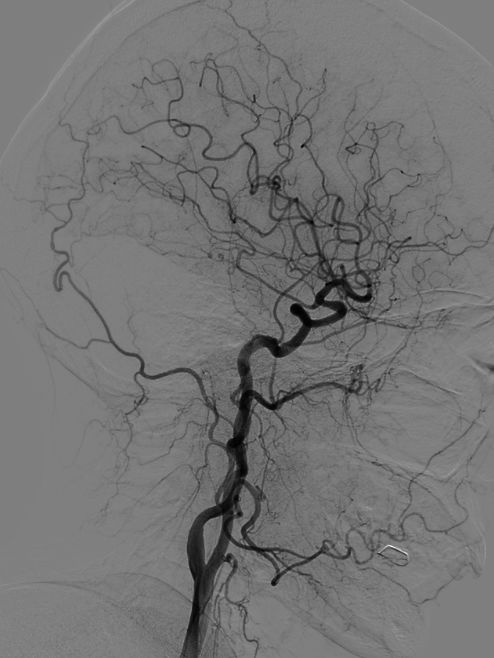

术后随访:

术后6个月复查造影示:动脉瘤不显影,血管重建效果令人满意。

随访结果:

术后6个月复查动脉瘤完全闭塞,局部血管重建。